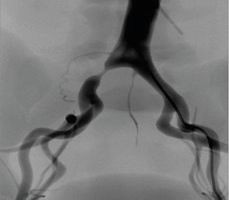

髂動脈介入手術(shù)模塊

可練習(xí)髂動脈支架手術(shù)的完整過程:造影診斷、導(dǎo)絲通過、導(dǎo)引導(dǎo)管的放置、預(yù)擴張、自擴張支架放置、后擴張、以及再造影等